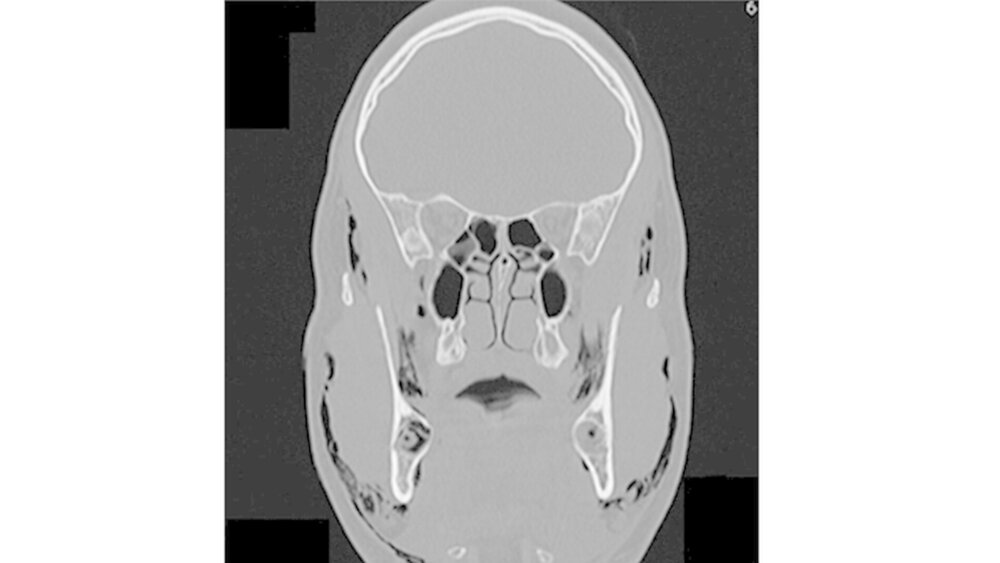

Permanent wiederholte er das Valsalva-Manöver, indem er Atemluft gegen seine verschlossenen Lippen presste. Bei der Aufnahme war der Patient hämodynamisch stabil. Die Funktionen von Nervus facialis sowie Nervus trigeminius waren normal. Auch die Entzündungswerte befanden sich im normalen Bereich. Klinisch war eine umfangreiche Schwellung im gesamten Gesichtsbereich sichtbar. Zudem hatte der Patient Schwierigkeiten, die Augen zu öffnen (Abbildungen 1 und 2).

Bei der Palpation war eine offensichtliche Schwellung der Periorbitalregion, der Wangen sowie der Supraklavikulargruben tastbar. Der enorale Befund zeigte eine nicht vollständig geschlossene Extraktionsalveole. Eine Entzündung war jedoch nicht zu erkennen. Mundboden und Rachenbereich waren von der Luftansammlung nicht betroffen. Der Patient konnte schlucken, doch das Atmen fiel im schwer.